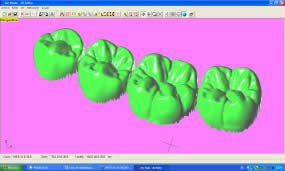

Introducción.- En oclusión, existen varios campos de aplicación básica para la digitalización. Hablamos, preferentemente, de la digitali- zación tridimensional. Recordemos que esta palabra es sinónimo de medición y –como tal- auxilio en esta rama odontológica tan necesitada de precisión. La digitalización tridimensional consistirá en el registro de la posición espacial, de un finito número de puntos, determinando sus coordenadas -x,y,z-. A menor distancia entre cada punto se conseguirá como resultado un objeto virtual con mayor detalle, coincidente con el real. Con cada triada se podrá formar una superficie, que continuada con la generada por el resto de la malla de puntos, completarán la forma del objeto. Este es el origen de donde partimos para establecer el concepto básico de las revolucionarias aplicaciones 3D. Se parte así del denominado escaneado tridimensional: Escaneado Superficial de un objeto real -> “Nube de Puntos” -> “Malla de Alambre” -> Superficie del Objeto Virtual. Con los modelos dentarios, impresiones o registros de oclusión, virtuales (en la pantalla del ordenador), realizaremos ahora, mediante un programa informático, la manipulación simulada, mediante computadora, para la realización del estudio y diseño de la oclusión. La Oclusión Computarizada (OC) –dentro de la más amplia Odontología Computarizada- comprende, hoy, fundamentalmente, tres fines: 1º)- El Estudio, Diagnóstico y Plan de Tratamiento Asistidos por Ordenador. 2º)- El Encerado Computarizado. (Por RP –Rapid Prototyping-, Prototipado Rápido, o por CAM –Computer Assisted or Aided Machining or Manufacturing-, Maquinado Asistido o Ayudado por Computador). 3º)- La Restauración y Confección de Prótesis Computarizada. (Por CAD-CAM, -Computer Assisted Design – Computer Assisted Manufacturing-, Diseño y Fabricación Asistidas por Computador). La Odontología Computarizada tiene entre sus numerosas secciones, ésta de oclusión, considerada primordial en el trabajo clínico habitual, desde la que nos relacionamos con la ortodoncia, cirugía implantológica, tecnología protésica y prostodoncia. Cada uno de los citados fines de la OC necesita partir de un escaneado tridimensional de los objetos a tratar: elementos del sistema dentario (arcadas) –de forma directa, en la misma boca del paciente-, o modelos dentales obtenidos por una impresión material de éstas y su posterior escaneado –o forma indirecta, fuera de la boca del paciente-. El escaneado se puede realizar con variados dispositivos, resultando procedimientos de distintos tipos y con diferentes características, clasificados simplificadamente como: A) Escaneado de contacto, háptico: B) Escaneado sin contacto: Tomando una imagen del objeto, marcado por líneas o cuadrículas luminosas proyectadas sobre su superficie, que se deforman con ella, analizándose luego digitalmente. El escaner se considera aquí un analizador trigonométrico del objeto, que registra su imagen, marcada mediante un rayado por luz –normalmente láser- (que permite, mediante software, obtener las coordenadas espaciales de multitud de puntos, que son agrupados en unidades de tres, constituyendo los vértices de una superficie triangular, que sumándose a las vecinas, llegarán a representar la envuelta completa del objeto y así su forma volumétrica o tridimensional). C) Combinado. Externo e Interno. Los escáneres suelen resultar, actualmente, poco económicos, y aunque van decreciendo en coste, están –para estas fechas- en un nivel que suele partir como mínimo de los 8.000 euros; siempre dependiendo del procedimiento de registro empleado, tamaño y precisión del escaneado. Existen: A) aparatos integrados en sistemas dentales, desarrollados específicamente para nuestro campo, de comprobada eficacia y de alto coste económico; B) dispositivos de uso general, aplicables a los propósitos de la odontología, de complicada adaptación pero de muy bajo coste relativo; C) múltiples posibilidades para la construcción de un escaner propio, casero y económico, que pueda, con suficiente experiencia, llegar a funcionar para uso profesional, gracias a la existencia de suficiente información de la tecnología empleada, ampliamente divulgada y de fácil desarrollo; útiles para fines diagnósticos. En oclusión necesitamos el 3D, pero también el 4D. Sumamos aquí a las tres coordenadas espaciales de cada punto del objeto, otra más, la cuarta dimensión: el tiempo. Dado que un objeto móvil, lo es por la temporalidad de sus posiciones en el espacio. Así se registrarán y analizarán digitalmente los movimientos mandibulares para conseguir la articulación y reproducción de la función masticatoria. Para esto se han aplicado determinados registros, mediante sensores de posición o por receptores de actividad muscular, como los electromiógrafos, o el más específico articulador virtual, del que se encuentran diferentes productos de software, englobados –como complemento necesario- en los programas que acompañan a los distintos sistemas de cad-cam dental. Desde el escaneado, o transformación u obtención del objeto real en cuerpo 3D, numérico, adquirido para ser estudiado y manipulado de forma digital, virtual, en el computador, continuamos con otras vías, ahora posibles, de enorme potencial, desde el estudio y planificación a la fabricación protésica. Así van a ser expuestas a continuación: A) La planificación; B) el encerado; y C) la fabricación. A) -Estudio, Diagnóstico y Plan de Tratamiento Asistidos por Ordenador. La planificación de la rehabilitación oclusal, puede iniciarse: A-1) Por Registro Estático Morfológico Computarizado, del aparato estomatognático y sistema dentario. Que puede realizarse: I) A partir de Escaneado Extraoral. I-a) Escaneado Volumétrico (CT–tomografía computarizada-) (O mejor, CBCT –tomografía computarizada de haz cónico-, de menor radiación y coste, con aparatos diseñados específicamente para uso dento-máxilo-facial ). I-b) Escaneado Superficial –de los modelos de estudio- y Registros Oclusales-. II) A partir de Escaneado Intraoral. II-a) Escaneado Volumétrico (CT local, o CBCT local, que se están desarrollando para aplicación retroalveolar). II-b) Escaneado Superficial –de las caras oclusales del sistema dentario-. A-2) Por Registro (Estático Morfológico Computarizado) de Huellas de Oclusión (o Registros Oclusales), para análisis de contactos intermaxilares, estáticos -y menos o indirectamente los movimientos mandibulares-. Mediante escaneado superficial de registros, sus modelos 3D, y combinación o no, con el Papel de Articular Electrónico (T-Scan). A-3) Por Registro Dinámico Funcional (fisiológico) Computarizado: I) Registro Computarizado (Integrado) de los Movimientos Mandibulares –electropantográfico o cinematográfico-. Por sensores o marcadores de posición. II) Registro Computarizado (Integrado) de la Función Muscular –electromiográfico-. A-4) Por Integración Informática de varios de los Registros citados. B) -Encerado Computarizado. Es el modelado o diseño virtual en la pantalla del ordenador y su realización en material de patronaje (como la cera u otro de similar; económico, modificable, transformable y rápido), que puede realizarse por: B-1) Por RP –prototipado aditivo- o B-2) por CAM –maquinado sustractivo-. Como pensamos en el concepto clásico, la realización de un encerado diagnóstico es clave para una rehabilitación oclusal correcta. Además el encerado servirá para la confección de: a) una posible férula radiológica y quirúrgica, b) una referencia para el tallado, la prótesis o rehabilitación temporal y el patrón para la definitiva. Se llevará a cabo, en dos etapas: 1ª) Etapa de creación del patrón. Elaboración virtual en la pantalla del ordenador. Necesitando el software apropiado, CAD. 2ª) Etapa de confección. Elaboración Real, mediante RP o CAM. 1ª) La etapa de creación virtual del patrón en la pantalla del ordenador, mediante un programa informático de diseño y manejo de objetos tridimensionales, (siempre partiendo de un registro previo, como el escaneado de los modelos), puede facilitarse con varias herramientas para: -Elaboración Virtual por Adición. 2ª) La etapa de confección, o elaboración real, mediante RP o CAM. -Confección por RP (Rapid Prototyping) –Prototipado Rápido-, de adición o construcción capa a capa, añadiendo una sustancia que se endurece, aumentando su nivel en superficie. La elaboración real por adición, es posible en un variado –pero limitado- tipo de materiales. -Confección por CAM (Computer Aided Machining) –Maquinado o Tallado Asistido por Ordenador-, de eliminación de sustancia o esculpido en un bloque sólido. La elaboración real por sustracción, es posible en un numeroso -y casi ilimitado- tipo de materiales. Existen gran cantidad de dispositivos que consiguen la fabricación y consecución física de un encerado real, a partir de su elaboración virtual, desde un escaneado y su diseño computarizado. Todos los sistemas denominados de cad-cam dental, en general, aunque no estén espe- cialmente dispuestos para ello, pueden dedicarse a este propósito; simplemente colocando un material de patronaje, como la cera, en lugar del material con el que se constituirá la prótesis definitiva. Pero, existen –también- sistemas espe- cialmente configurados para el trabajo en material de diseño, normalmente: ceras, resinas o compuestos, es lo que se denomina prototipado rápido (rapid prototyping). En la industria general, la fabricación de cualquier objeto en serie, requiere de estos procedimientos en las primeras etapas de elaboración para su producción. La más económica y reducida Impresora 3D o Sistema de Prototipado Rápido, que puede confeccionarnos unos maxilares, a partir de la tomografía, o un encerado diagnóstico, según el software disponible. Su precio actual 45.000 Euros. C) -Restauración y Confección de Prótesis Computarizada. (Por CAD-CAM). Es el modelado o diseño virtual en la pantalla del ordenador y su realización en material definitivo (como porcelana, titanio, aleación preciosa, u otro similar); poco económico, difícilmente o no modificable, ni transformable y que requiere de un tiempo adecuado, mucho mayor que el requerido para la confección del patrón de material plástico. Esto puede realizarse por numerosos dispositivos. Existen gran variedad de sistemas para el diseño y confección de restauraciones y prótesis. Son los denominados gene- ralmente SISTEMAS DE CAD-CAM DEN- TAL (Dental Cad-Cam System): (Entre estos sistemas encontramos los que también pueden planificar el tratamiento restaurativo y realizar el encerado diagnóstico con diseño y confección de un patrón oclusal; como hemos referido antes). Históricamente estos sistemas comenzaron con la década de los setenta -en 1971, con el Holodontography-Altschuler System-, y con el Sopha System de Duret, progresando enormemente hasta comienzos de los noventa. Durante esos veinte años, se potenció su desarrollo con el siguiente hito histórico que los encumbró, en su segunda década, por la aparición de los principales impulsores del cad-cam clínico comercializable -Mörmann y Brandestini, en 1981-, denominado Sistema Cerec. También se establecieron los principios de estos dispositivos con el DCS Dental System, el CAP System, el Minnesota-Rekow System, el Nissan Cad/Cam System, Automill y Microdenta System. El culmen del progreso se alcanzó a mediados de los noventa, con sistemas ampliamente comercializados y evolucionados hasta hoy: Procera, DCS Dental, o Cicero. En los siguientes diez años, se continuó perfeccionando los sistemas citados; hubo algunos sistemas no comerciales o de escasa difusión, o distribuidos moderadamente; repre- sentando un período hasta el 2000, con una pequeña depresión, en los años medios, por el declive en la extensión de estos productos, en relación al extraordinario futuro que se les auguraba, motivada por el alto coste de los equipos y las limitaciones en su potencia digital, en el que –aún y así- aparecieron sistemas como: Belledent, Cadim, Dentscan, CCD System, Cynovad, Digident-Girrbach, Decim y Etkon. La segunda revolución para la odontología por cad-cam se produjo con el comienzo del siglo. Ampliándose enormemente la cantidad de sistemas y alentándose una explosión del trabajo digital en odontología, con: Cercon-Degussa, Lava-3M-Espe, Cad-Esthetics System-Ivoclar, DDS, GC-Dental, Everest-Kavo y Bego. En estos momentos el futuro de la odontología se encuentra inexorablemente unido a estos aparatos. Para el clínico o el laboratorio dental es hoy imprescindible contar con ellos. Siguen nuevas apariciones, como el sistema Hint-Els, o el Evolution-4D, similar al Cerec, que fue el pionero, pero que todavía, a la fecha, se mantiene como el más versátil, modulable y práctico, con progresos como el facilitado trabajo de diseño tridimensional o el nuevo escaneado extraoral independiente. Los sistemas de cad-cam, están integrados por: un escaner que digitaliza el objeto dental, un ordenador con el software adecuado para el diseño virtual, y una máquina de tallado para la fabricación del objeto diseñado en un material determinado. Una relación actualizada, de gran número de los sistemas existentes se encuentra en “Aktuelle CAD/CAM Systeme”, en http://www.tu-dresden.de/medprothetik/computerzahn/CAD-CAM-Systeme.htm Factores clave en la Oclusión Computarizada-. La digitalización del estudio, diagnóstico y tratamiento de la oclusión, como la construcción o restauración de un sistema dentario óptimo para la correcta función masticatoria del aparato estomatognático, pretende facilitar y generalizar la excelencia en el trabajo clínico. Es una aplicación de preferencia informática porque pueden manejarse gran cantidad de datos, mediciones, relaciones geométricas, unidas a la tridimensionalidad y la movilidad de sus elementos, de una forma racional, lógica y científicamente fundamentada, aún partiendo de concepciones filosóficas o criterios sujetos a distintas escuelas de oclusodoncia. La digitalización de la oclusión pude llevar- nos a despejar supuestos sin evidencia científica, de la que adolece sectorialmente nuestro arte. Tenemos suficientes fórmulas, reglas y relaciones numéricas, aportadas por numerosos autores, que tienen que se recopiladas y que pueden así ser aplicadas. Yá que la digitalización recoge todos los datos métricos y posicionales (coordenadas de cada punto, con su x,y,z), del sistema dentario, se pueden establecer fórmulas matemáticas para que -siendo la z la determinante de la altura de un punto en el espacio-: una z máxima, de una pieza mandibular, esté más o menos próxima a una z mínima de una pieza maxilar; que un punto (de cúspide) -con una determinada x,y- maxilar, coincida con otro –con la misma x,y- mandibular, pero con distintas aunque casi idénticas z, dándose el contacto oclusal. Y de esta forma, con sucesivas relaciones (matemáticas) se construiría una oclusión tendente a la excelencia; matemáticamente desarrollada. Así podría confeccionarse, automáticamente, una oclusión geométrica, dando, por ejemplo, solamente: la posición base de cada pieza, la x,y de las cúspides de una hemiarcada, y la altura de su plano oclusal, y automáticamente se generarían las cúspides agonistas y antagonistas, y la morfología dental completa de ambas arcadas. Se tendrían que añadir los datos correspondientes a los dientes anteriores, a las ATMs y las fórmulas de relación de las pendientes. Distintos autores han desarrollado relaciones métricas en oclusión. Algunos han simplificado el proceso, como partida, para ir añadiendo variantes; así, pueden usarse valores standard, normales, del ángulo cuspídeo para fabricar la morfología oclusal en CAD/CAM, -cuando la creación del esquema oclusal es de novo-, según Hobo y Takayama; y el uso de varios valores fijos de partida, universalmente aceptados, en lugar de la medida directa de la pendiente condilar es, según los mismos autores, muy importante en el desarrollo extenso de los sistemas de CAD/CAM. Así, el procedimiento de «twin-stage» propuesto por estos autores, en su libro “Oral Rehabilitation”, proporciona una solución en la producción de una oclusión dinámica tridimensional para el CAD/CAM. Otra técnica, consiste en el encerado virtual, mediante un modelado CAM, siguiendo las etapas de Shillimburg, o Kuwata, elaborando paso a paso la morfología oclusal, orientada a su enfrentamiento con el antagonista, encaminando los volúmenes cuspídeos como en el encerado progresivo clásico, gota a gota. Se realizaría su construcción virtual en la pantalla del ordenador, pudiendo estar facilitada su manipulación, mediante “espátulas de encerado virtual”, utilizando los digitalizadores de brazo articulado, con los que se pueden disponer los volúmenes necesarios, en la posición espacial que se desee. No obstante, el modelado dental se puede realizar siempre, aunque sea a través del clásico ratón del ordenador, de forma virtual, con la imagen tridimensional en la pantalla, utilizando diferentes procedimientos, con el software adecuado: A) Automático, a partir de las reglas dentométricas, odontométricas y cefalométricas, relacionadas con la gnatología, tomando previamente los valores claves necesarios del paciente. B) Mediante diseño de la anatomía con trazado de los perfiles, líneas y curvas, que van a definir las superficies dentales. Trabajando bidimensionalmente, en base a cortes de la estructura a construir, que manipulada variando sus dos dimensiones, va a corresponderse con la morfología dental tridimensional, al establecerse un área de influencia y cambio en los cortes vecinos, y así alterándose el volumen dental completo. Este era el procedimiento de variación anatómica utilizado, durante dos décadas con el Sistema Cerec (el Cerec 1, Cerec 2 y Cerec 3), hasta la llegada del Cerec 3D. C) Mediante copiado de la cara oclusal ideal, realizada previamente en cera u otro material real, del diente, su registro oclusal o su antagonista, en el concepto original del Sistema CEREC, de construcción oclusal mediante Correlación –copiando un encerado previo- o Función –correspondiendo automáticamente a la cara oclusal del antagonista-. D) Mediante selección de dientes, individuales o en grupo (incisivos, caninos, premolares, molares, arcadas, hemiarcadas, sistema dentario, maxilares o mandibulares), de entre un grupo de archivos de modelos dentales tridimensionales virtuales, como una librería de objetos 3D. Como en la selección de las tablillas de dientes para la confección de las prótesis completas. Escogiendo tamaño y forma. Colocando cada pieza o bloque en su lugar, con la disposición espacial y oclusal correspondiente. E) Mediante la misma selección, antes citada, seguida luego de una transformación, como estiramiento o estrechamiento, u otras variaciones morfológicas, con las herramientas de edición del programa informático, hasta conseguir la oclusión que se pretende. F) Mediante encerado virtual, de adición progresiva de volúmenes anatómicos, en el concepto clásico de encerado gota a gota, con la metódica de P. K. Thomas, para restauraciones parciales, o de Kuwata, para rehabilitaciones extensas. El método de encerado es el que nos permitirá la construcción de una oclusión individualizada. Pero la necesidad de utilización de un articulador es evidente. Es presumible que se desarrollen nuevos instrumentos para la perfección de la oclusión computarizada, semejantes a los articuladores mecánicos tradicionales. Serán los denominados articuladores virtuales, (VA –Virtual Articulator-), o simuladores digitales de la articulación oclusal, consistentes en un programa informático, capaz de relacionar los modelos virtuales, permitiendo movimientos similares a los naturales del paciente: es la aplicación de la tecnología de la realidad virtual a la oclusión (VR –Virtual Reality-). Esto es lo que nos permitirá pasar de la fórmula empleada generalmente para el modelado oclusal, que suele ser estática y referida a un registro de las superficies antagonistas, a un sistema experto que reproduzca la relación completa de ambas arcadas, las articulaciones, y su combinación con los movimientos masticatorios: realizando la dinámica mandibular. Hoy en la mayoría de los sistemas de cad-cam, los trabajos oclusales se realizan, extensamente, basados sólo en el enfrentamiento con el antagonista, sin tener en cuenta la movilidad mandibular, las guias condilares o anteriores. Es como si realizásemos un encerado oclusal sin tener en cuenta los determinantes anteriores y posteriores, y trabajásemos en un articulador, no ajustable, o simplemente en un Oclusor o Verticulator, sin giro de cierre ni desplazamientos horizontales.El articulador virtual, por software, para el diseño oclusal en la pantalla del ordenador, aún no es empleado de forma generalizada en estos sistemas, pero ya se encuentran como aplicaciones en algunos de ellos. Uno de los pioneros se utiliza en el sistema Cynovad. Aquí, directamente relacionado con la confección de un encerado oclusal. Otros dispositivos electrónicos y digitales, de registro por ordenador, que podrían combinarse con la construcción plástica de la oclusión, en cera u otro material, solo se están utilizando para diagnóstico, o como complementos a articuladores mecánicos sofisticados; así podemos encontrar programas como Rosy32 Robot System (Diagnostic Articulator), de registro dinámico, el VirtSet, de diagnóstico y predicción oclusal-ortodóntica, o el ArtiKulator-Software (ver ArtiDemo), de programación virtual de un articulador, con elección del equivalente mecánico real (Sam, Artex, Kavo,…). Entre éstos, el sistema más completo desarrollado, con escaneado de modelos y registros, y correspondencia con la dinámica mandibular, obtenida por un arco facial cinemático, con sensores de posición y movimiento, es el DentCAM.Para clasificar los instrumentos de oclusión, consideramos muy completa la clasificación de los articuladores mecánicos, desarrollada en The International Workshop Occlusion, de 1972, University of Michigan: 1) Clase I – Sujetadores simples de modelos. Subdivisión A (Con movimientos verticales; Corelator, Verticulator). Subdiv. B (Con articulación de bisagra sin desplazamientos horizontales; Centric Relator). Conclusiones (parciales para esta primera parte).- El articulador virtual podría establecerse a partir del escaneado de un articulador mecánico seleccionado, a partir de un modelo construido íntegramente por CAD de forma virtual, o –idealmente- a partir de un patrón anatómico, individual, a partir de la radiología tridimensional (como la Tomografía Computarizada). A estas estructuras se les sumarán los datos necesarios para la función: relación intermaxilar –estática- (oclusal) y relación cráneo-mandibular dinámica (pendiente condílea y Bennett), con ayuda también del registro de la actividad muscular (electromiografía). A la clasificación de los articuladores antes expuesta, le podemos añadir ahora el Tipo V, constituido por los Articuladores Virtuales, o instrumentos informáticos que pueden reproducir la oclusión dental en el ámbito de la realidad virtual, que se desarrollan como programas informáticos concretos, de muy variada composición en sus elementos de software, y distintos por los diferentes tipos de registros que necesitan para su efectiva y precisa actuación. Dentro de este V grupo, a su vez, podríamos –paralelamente a la clasificación de los articuladores mecánicos-, establecer tantas subclases como las de los tipos y subclases de aquellos. Así habría de clase I, como ocurre mayoritariamente en los sistemas de Cad-Cam dental actuales, cuando utilizamos modelos dentales 3D y registros estáticos de antagonistas. Es éste el cambio que se experimentará en los próximos años, en la Oclusión Computarizada: la utilización generalizada de Articuladores Virtuales de clase III y IV. Bibliografía Cooper BC. Parameters of an optimal physiological state of the masticatory system: the results of a survey of practitioners using computerized measurement devices. Cranio. 2004 Jul;22(3):220-33. Reiss B. Occlusal surface design with Cerec 3D. Int J Comput Dent. 2003 Oct;6(4):333-42 Petrie CS, Woolsey GD, Williams K. Comparison of recordings obtained with computerized axiography and mechanical pantography at 2 time intervals. J Prosthodont. 2003 Jun;12(2):102-10. Kojima T, Sohmura T, Nagao M, Wakabayashi K, Nakamura T, Takahashi J. A preliminary report on a computer-assisted dental cast analysis system used for the prosthodontic treatment. J Oral Rehabil. 2003 May;30(5):526-31 Bernhardt O, Kuppers N, Rosin M, Meyer G. Comparative tests of arbitrary and kinematic transverse horizontal axis recordings of mandibular movements. J Prosthet Dent. 2003 Feb;89(2):175-9 Tsai HH. A computerized analysis of dental arch morphology in early permanent dentition. ASDC J Dent Child. 2002 Sep-Dec;69(3):259-65, 234 Ferrario VF, Sforza C, Serrao G, Schmitz JH. Three-dimensional assessment of the reliability of a postural face-bow transfer. J Prosthet Dent. 2002 Feb;87(2):210-5. Kerstein RB. Current applications of computerized occlusal analysis in dental medicine. Gen Dent. 2001 Sep-Oct;49(5):521-30 Kerstein RB, Wilkerson DW. Locating the centric relation prematurity with a computerized occlusal analysis system. Compend Contin Educ Dent. 2001 Jun;22(6):525-8, 530, 532 passim; quiz 536. Sohmura T, Kojima T, Wakabayashi K, Takahashi J. Use of an ultrahigh-speed laser scanner for constructing three-dimensional shapes of dentition and occlusion. J Prosthet Dent. 2000 Sep;84(3):345-52. Kerstein RB. Computerized occlusal management of a fixed/detachable implant prosthesis. Pract Periodontics Aesthet Dent. 1999 Nov-Dec;11(9):1093-102 Tarantola GJ. A computerized model for teaching various methods of positioning the condyles to centric relation. Gen Dent. 1999 May-Jun;47(3):308-12 Gsellmann B, Schmid-Schwap M, Piehslinger E, Slavicek R. Lengths of condylar pathways measured with computerized axiography (CADIAX) and occlusal index in patients and volunteers. J Oral Rehabil. 1998 Feb;25(2):146-52 Tamaki K, Celar AG, Beyrer S, Aoki H. Reproduction of excursive tooth contact in an articulator with computerized axiography data. J Prosthet Dent. 1997 Oct;78(4):373-8 Garcia Cartagena A, Gonzalez Sequeros O, Garrido Garcia VC. Analysis of two methods for occlusal contact registration with the T-Scan system. J Oral Rehabil. 1997 Jun;24(6):426-32 Matsui Y, Ohno K, Michi K, Suzuki Y, Yamagata K. A computerized method for evaluating balance of occlusal load. J Oral Rehabil. 1996 Aug;23(8):530-5 Giddon DB, Sconzo R, Kinchen JA, Evans CA. Quantitative comparison of computerized discrete and animated profile preferences. Angle Orthod. 1996;66(6):441-8 Matsui Y, Neukam FW, Wichmann M, Ohno K. A computerized method for evaluating distribution of occlusal load on implant-supported fixed cantilever prostheses. Int J Oral Maxillofac Implants. 1996 Jan-Feb;11(1):67-72 Hayashi T, Saitoh A, Ishioka K, Miyakawa M. A computerized system for analyzing occlusal relations during mandibular movements. Int J Prosthodont. 1994 Mar-Apr;7(2):108-14 Maness WL. Computerized occlusal analysis. J Can Dent Assoc. 1993 Aug;59(8):701-2 Edwards CL, Richards MW, Billy EJ, Neilans LC. Using computerized cephalometrics to analyze the vertical dimension of occlusion. Int J Prosthodont. 1993 Jul-Aug;6(4):371-6 Giannazzo E, Leonardi R, Scivoli M, Rapisardi CB, Vassallo V. [Computerized parametrization in orthognathodontics] Boll Soc Ital Biol Sper. 1993 Jun;69(6):373-9 Harvey WL, Osborne JW, Hatch RA. A preliminary test of the replicability of a computerized occlusal analysis system. J Prosthet Dent. 1992 May;67(5):697-700 Boening KW, Walter MH. Computer-aided evaluation of occlusal load in complete dentures. J Prosthet Dent. 1992 Mar;67(3):339-44 Reza Moini M, Neff PA. Reproducibility of occlusal contacts utilizing a computerized instrument. Quintessence Int. 1991 May;22(5):357-60 Harvey WL, Hatch RA, Osborne JW. Computerized occlusal analysis: an evaluation of the sensors. J Prosthet Dent. 1991 Jan;65(1):89-92 Palano D, Molinari G, Salvo C. [Electromyography and computerized magnetic gnathokinesiography in the diagnosis and therapy of craniomandibular disorders] Minerva Stomatol. 1990 Dec;39(12):977-87